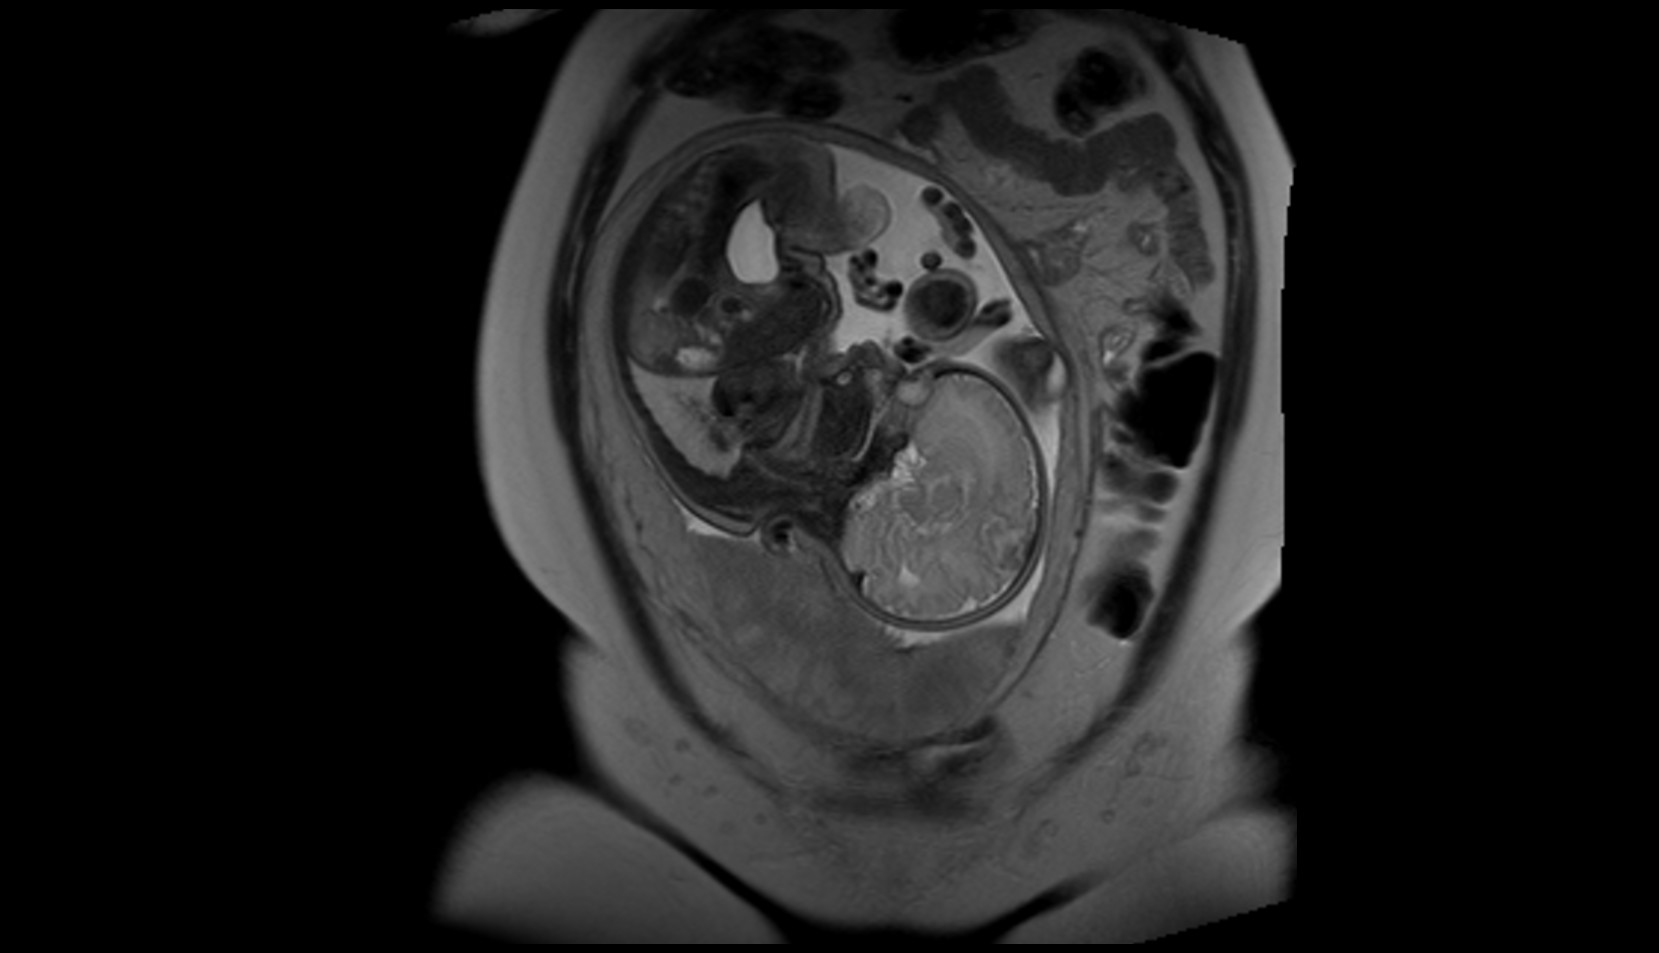

- Placenta

- Uterus (pregnancy)

- Amniotic fluid

- Umbilical cord

- Fetal Liver

- Fetal small bowel

- Fetal urinary bladder

- Fetal kidneys

- Fetal stomach